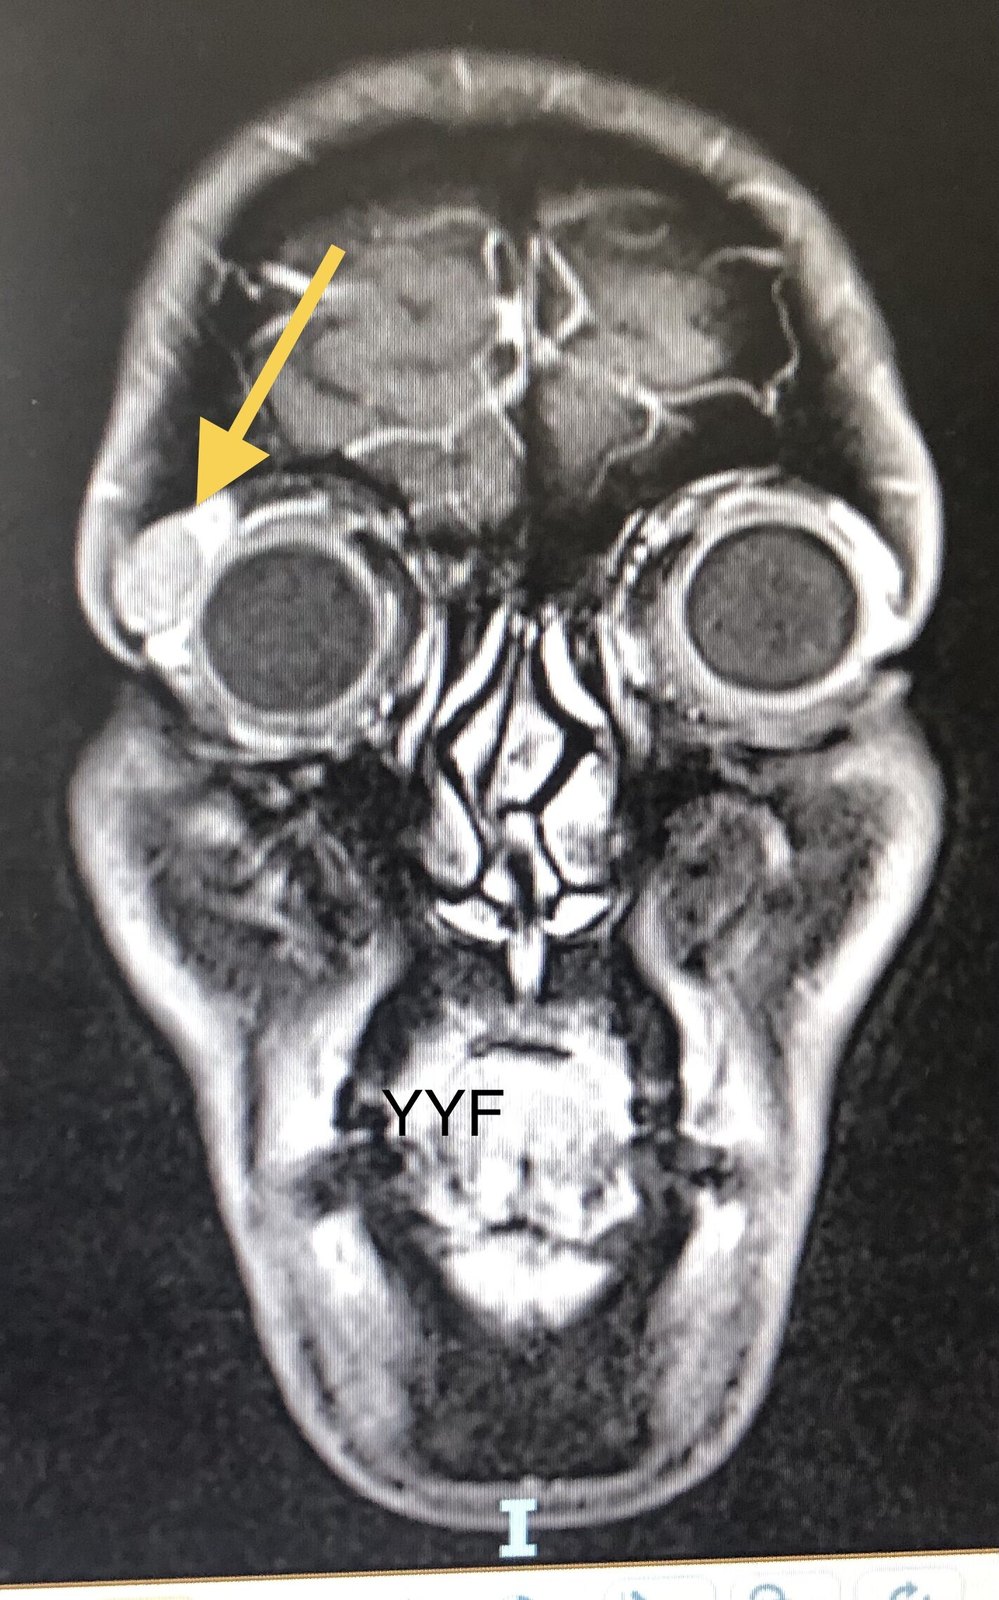

260.眼眶泪腺混合瘤的诊断和手术治疗&第一次手术完整摘除至关重要,因为复发后有可能恶变!

肿瘤典型形态,泪腺窝扩大但无骨破坏

其影像学具有典型特点,临床当中根据肿瘤的形态、肿瘤内是否有钙化、以及是否伴有对应的骨壁改变等判断肿物性质。

泪腺混合瘤的核磁共振表现